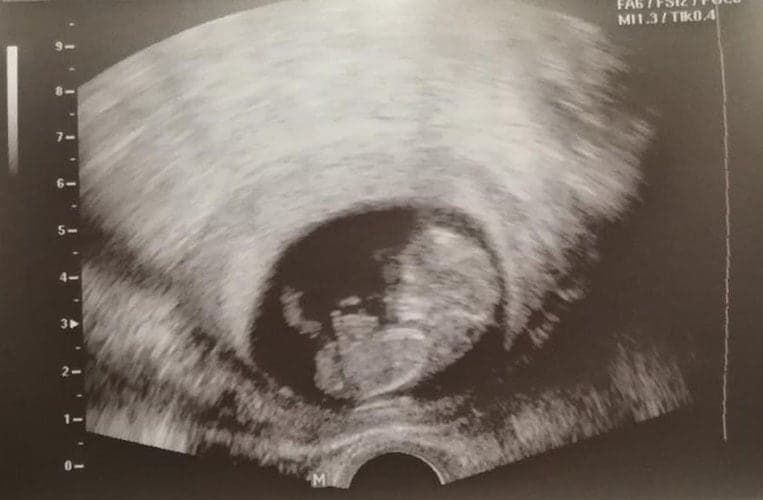

Ultraschallbilder aus dem 1. Trimester (1. SSW bis 12. SSW)

Im ersten Trimester sind die Ultraschallbilder meist noch schwer zu deuten. Oft erkennt man in den letzen Wochen des ersten Trimesters gut den Körper, den Kopf und die Gliedmaße. Das Geschlecht kann man in dieser Zeit meist noch nicht erkennen.